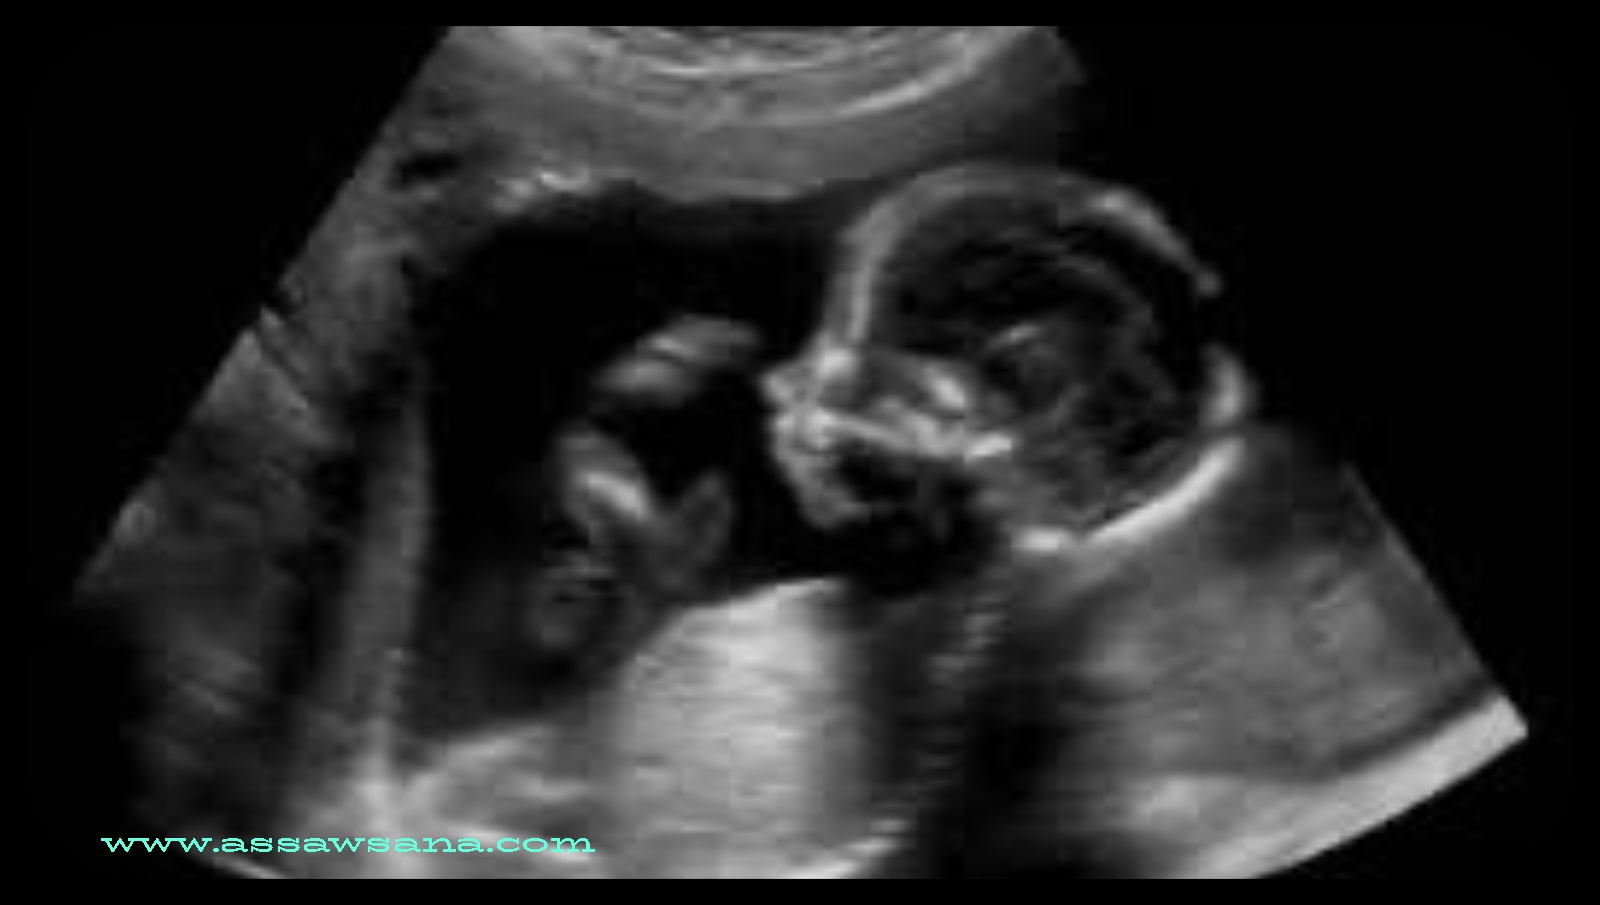

1- فحص الموجات فوق الصوتية

يُعدّ فحص الموجات فوق الصوتية أو الألتراساوند (Ultrasound) من أكثر الطرق الشائعة للكشف عن جنس الجنين، وعادةً ما يحدد الفحص جنس الطفل خلال الأسبوع 18-20 من الحمل. يُشار إلى أنّ الطبيب يقوم بهذا الفحص شهريًا للتأكد من صحة الأم وجنينها، كما يُساعد على قياس وزن الجنين، والسائل المحيط به، ومستوى ارتفاع المشيمة.